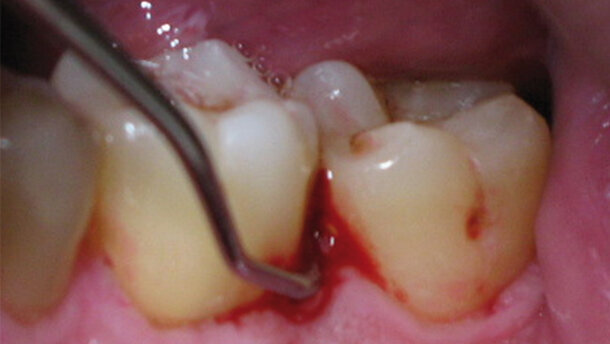

Negli ultimi anni, l’interesse della comunità scientifica si è lentamente spostato verso gli effetti dell’utilizzo della luce laser in alternativa o in aggiunta alle metodiche convenzionali. L’effettivo potere battericida di questa radiazione luminosa è stato di recente riportato in letteratura, sia attraverso studi in vitro che in vivo6. Nello specifico, il laser a diodi nei trattamenti parodontali, è stato proposto come strumento di ausilio alle tecniche standard dal momento che possiede un effetto antibatterico che è possibile ottenere anche in tasche profonde e anguste attraverso fibre ottiche di diametro molto sottili (fino a 300 micron)7. Lo scopo del lavoro è stato di monitorare i tipi di microrganismi e i relativi valori di carica microbica in pazienti parodontopatici trattati sia con tecniche tradizionali (Fig. 1) che con laser a diodi (Fig. 2) in aggiunta a tali tecniche.